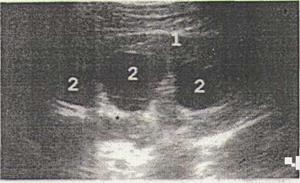

Рис. 3 Гидронефроз ІІ стадии: 1 - почка; 2 - чашечки. Собирательная система почки значительно расширена, наблюдаются признаки атрофии паренхимы.